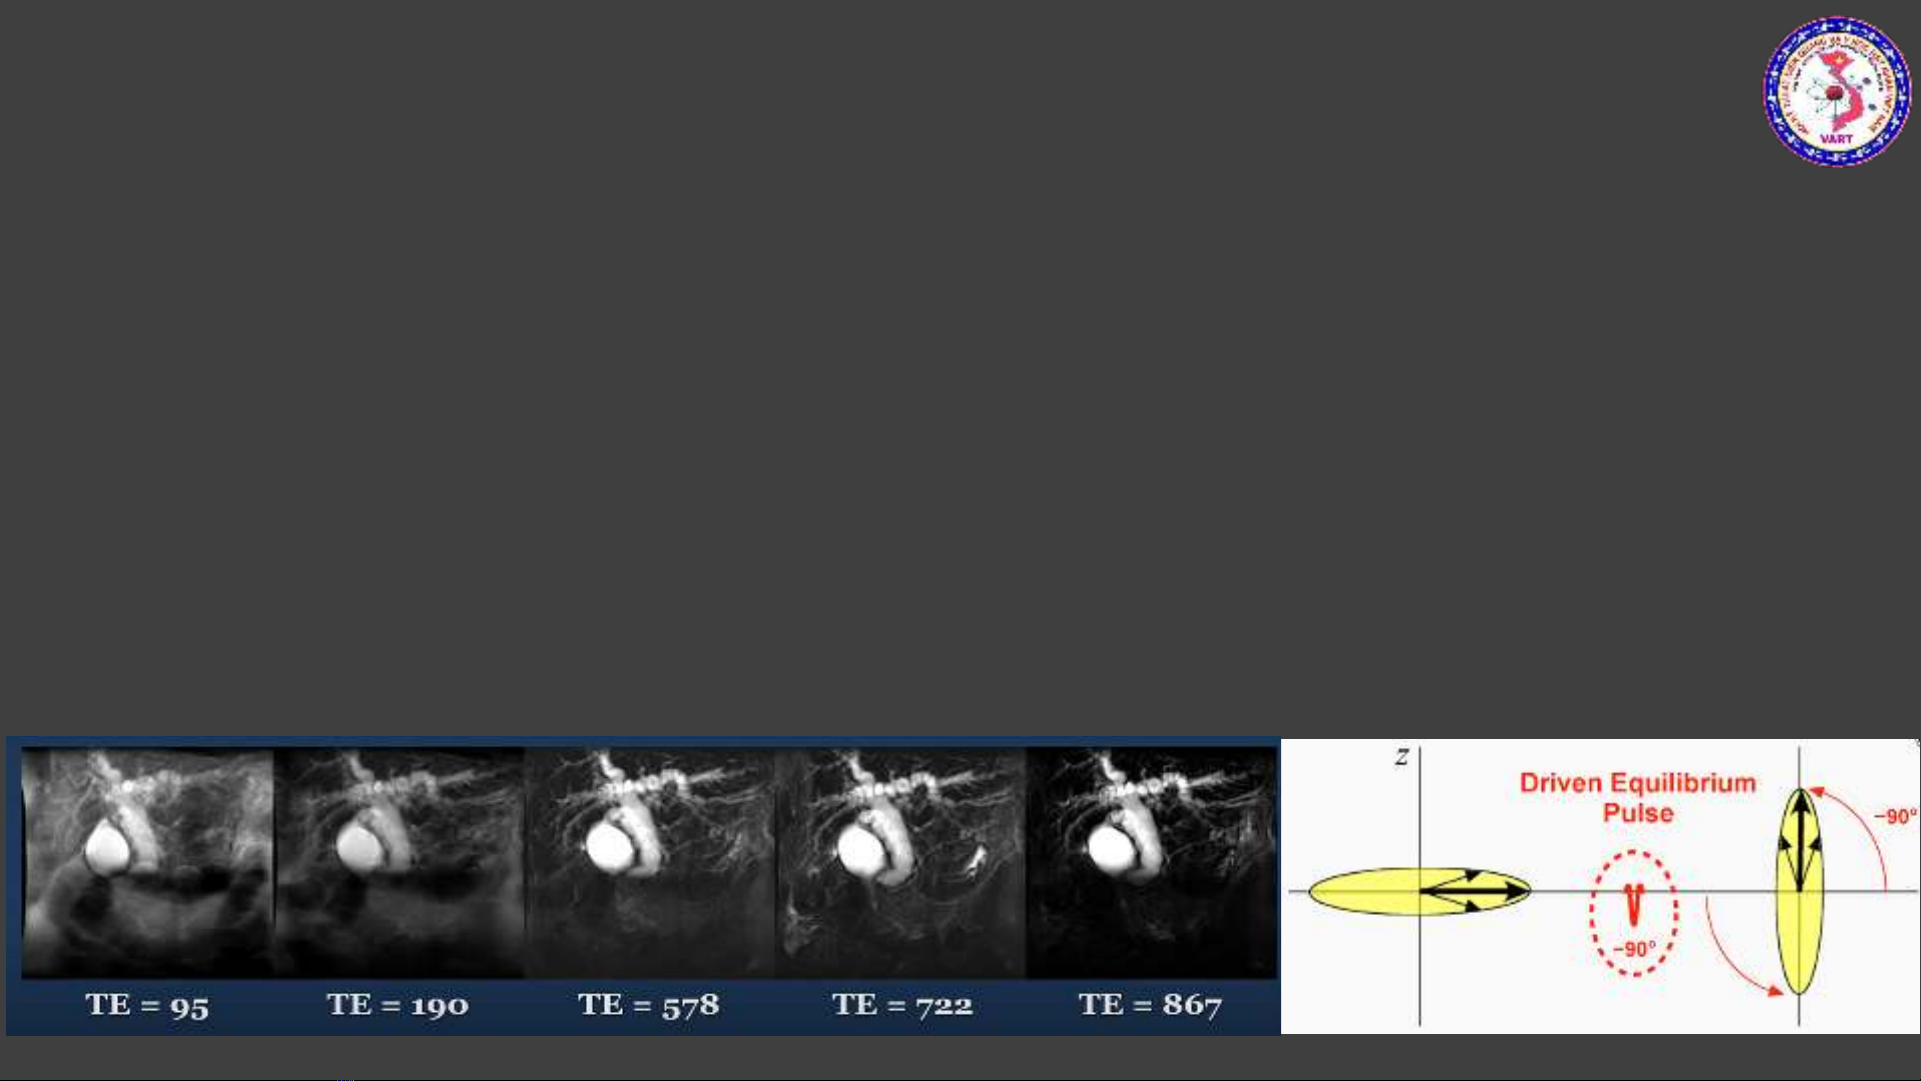

•Dựa trên nền tảng FSE 3D

•Sử dụng TE rất dài, từ 600-1200ms. Mục đích để các mô xung quanh bị bão hòa hoàn toàn, chỉ

còn lại những thành phần dịch tự do, dịch di chuyển chậm có thời gian T2 dài -> tăng tín hiệu

•Sử dụng kèm một kỹ thuật xóa mỡ để xóa nền tốt hơn (CHESS)

•Sử dụng xung “Fast Recovery” (Restore – Driven Equilibrium) -> duy trì tín hiệu cao của

dịch